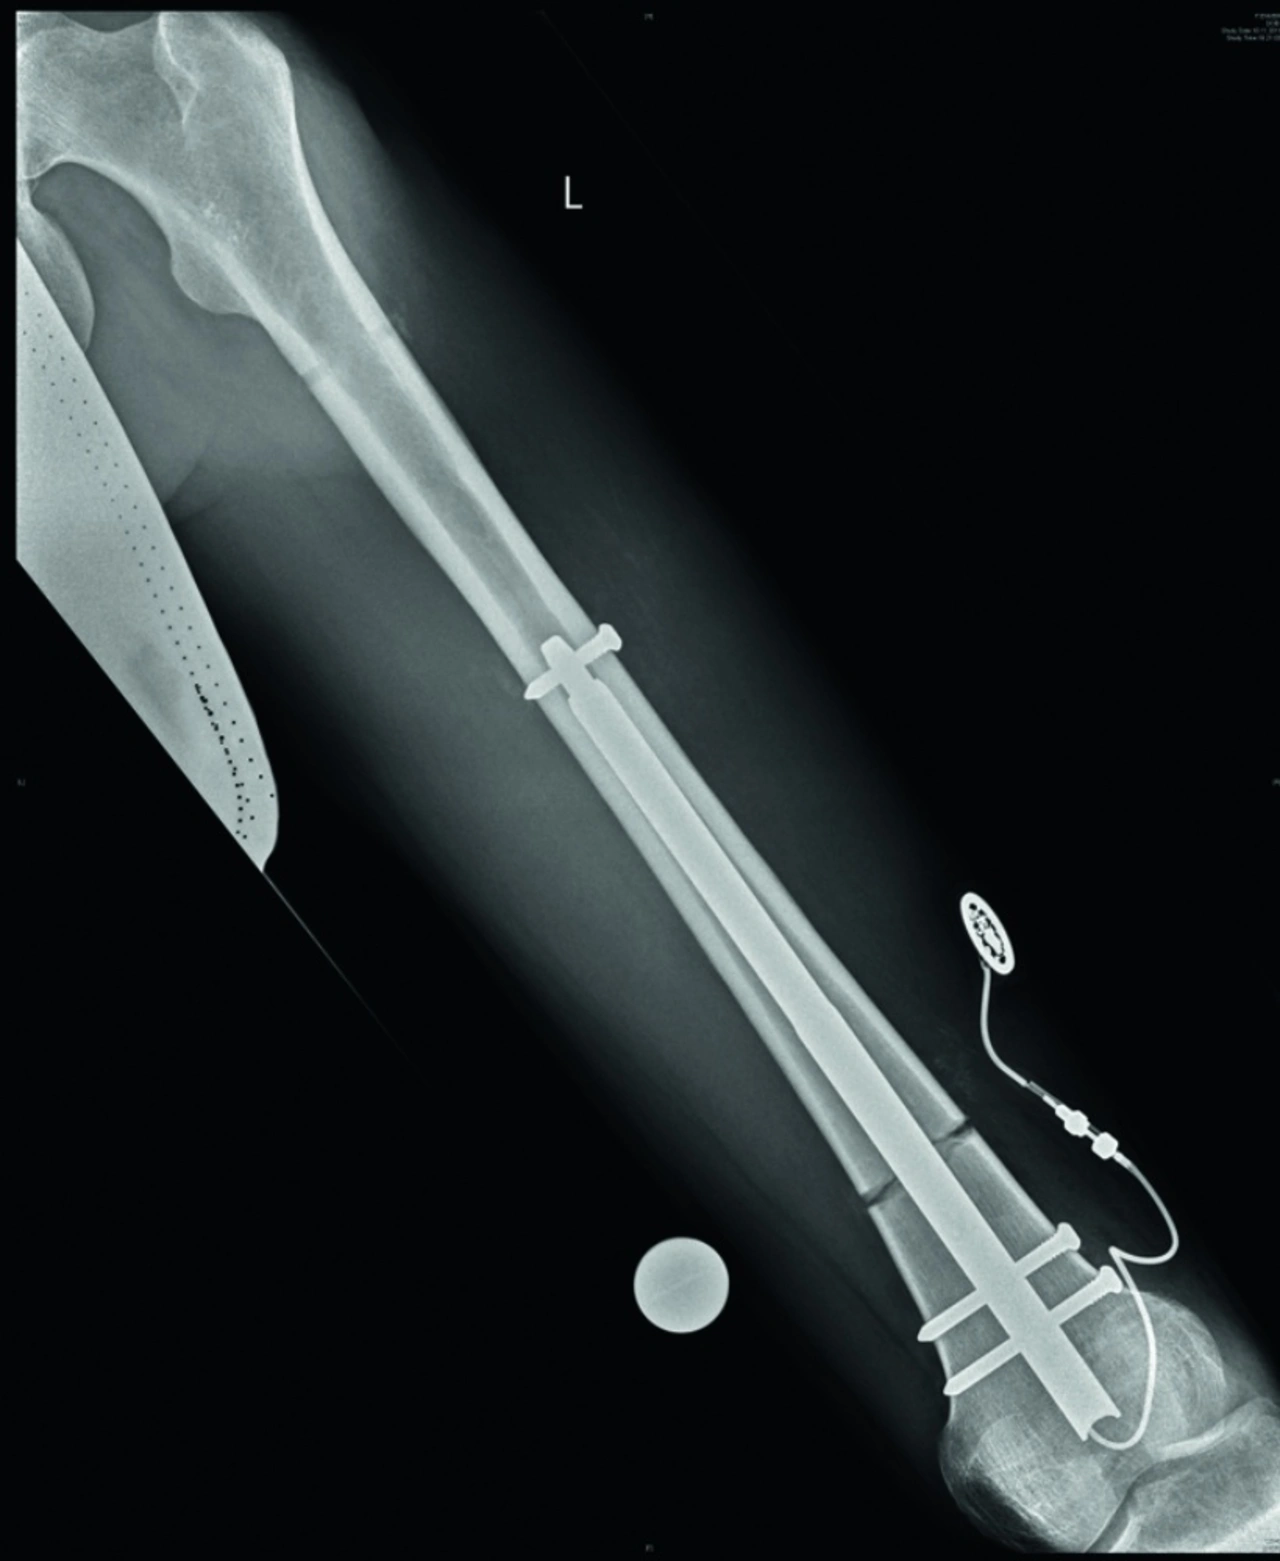

Der Verlängerungsmarknagel Fitbone wird bei Beinlängendifferenzen oder zur Korrektur von Achsfehlstellungen im Oberschenkel angewendet.

Elektronische Systeme, mit denen sich medizinische Behandlungen und Therapien durchführen und personalisieren lassen, sind eine der Visionen, die sich mit dem Begriff Medizin 4.0 verbinden lassen. Wittenstein Intens bildet diese Attribute in seinem Verlängerungsmark­nagel-System Fitbone zur Korrektur von Beinlängendifferenzen ab (Bild oben). Durch einen minimal invasiven chirurgischen Eingriff wird der Verlängerungsmarknagel in den Markraum des Knochens implantiert. Mithilfe eines kleinen und leichten Steuerungssets aktiviert der Patient selbstständig das System und somit die Verlängerung (Bild 1). Hierzu wird ein externer Transmitterkopf auf die Haut aufgelegt und – nach Starten einer Verlängerungssequenz – Energie an den unter der Haut befindlichen Receiver berührungslos übertragen. Aufgrund der Einfachheit des kleinen, leisen und portablen Steuerungssets sowie der kurzen Dauer können die Verlängerungen bequem auch während der Pausen im Büro oder in der Schule durchgeführt werden. Das System bietet jedoch nicht nur mehr Komfort, sondern minimiert Behandlungsdauer, Schmerzen sowie Infektionsrisiken und liefert auch aus kosmetischer Sicht ein ideales Ergebnis.

Operiert wird der Verlängerungsmarknagel ausschließlich durch geschulte Operateure, die in entsprechenden Workshops die Besonderheiten und die Implantationstechnik des Verlängerungsmark­nagels erlernen. Auf diese Weise wird für die Patienten von der ersten Kontaktaufnahme über Untersuchungen bis zur Explantation nach Abschluss der Behandlung eine optimale und ganzheitliche Betreuung sichergestellt. In Verbindung mit dem Verlängerungsmarknagel kommt eine neu entwickelte Baugruppe für die drahtlose Energieübertragung zum Einsatz, deren 3D-Aufbautechnologie beim Design Award 2016 des FED Fachverband Elektronik Design e. V. einen Spitzenplatz in der Kategorie 3D/Bauraum belegte. Der Receiver wird in das subkutane Fettgewebe direkt unter der Haut platziert, wodurch der induktive Energietransfer unabhängig von den Weichteilverhältnissen des Patienten sichergestellt ist (Bild 2). Die kontaktlose Energieübertragung zwischen dem Transmitterkopf und dem Receiver des Implantats nutzt elektromagnetische Felder, um den Verlängerungsmarknagel mit elektrischer Energie zu versorgen.